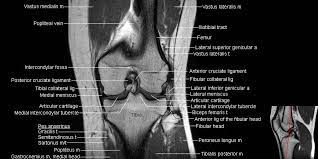

T2w axial fat sat 1. Stanford bone tumor ddx | iss/ssr msk lectures | ocad msk cases stanford msk mri atlas has served over 1,000,000 pages to users in over 100 countries. Abnormal anatomy with normal signal, i.e. Sagittal view is the basis for knee mri including acl evaluation. Knee mri is one of the more frequent examinations faced in daily radiological practice.

Mri knee anatomy scroll using the mouse wheel or the arrows. To improve delineation of acl, the knee is slightly flexed (see chap. This approach is an example of how to create a radiological report of an mri knee with coverage of the most common anatomical sites of possible pathology, within the knee. Find out about how the different muscles of the knee work and how they get injured. Magnetic resonance imaging is particularly well suited for the medical evaluation of the musculoskeletal (msk) system including the knee, shoulder, ankle, wrist and elbow. This mri knee sagittal cross sectional anatomy tool is absolutely free to use. Accessory muscles are isointense to skeletal muscle on all pulse sequences and typically attach by muscular or tendinous insertions. Anatomy of the knee can be complicated and hard to understand.

Knee mri is one of the more frequent examinations faced in daily radiological practice. Naturally, in order to assess pathologic knee imaging, it is necessary to know the appearance of a normal knee mri. Anatomical structures of the lower limb (hip, thigh, knee, leg, ankle and foot) and specific regions (compartment of the lower. A tendon connects the muscle to the bone. Stanford bone tumor ddx | iss/ssr msk lectures | ocad msk cases stanford msk mri atlas has served over 1,000,000 pages to users in over 100 countries. Atlas of knee mri anatomy. Use the mouse scroll wheel to move the images up and down alternatively use the tiny arrows (>>) on both side of the image to move the images. Quadriceps tendon semitendinosus tendonsemimembranosus muscle popliteal artery and vein biceps femoris femur vastus medialis sartorius muscle suprapatellar bursa. 12 photos of the knee muscle anatomy mri. Both the pronounced accuracy of the mri and the high prevalence of knee disorders, makes the knee mri the most frequently ordered imaging procedure of the musculoskeletal system. The knee joint is most significantly affected by two major muscle groups: If the slice thickness is 3 mm or so, it is not possible to visualize acl and pcl in their entire lengths in one plane. Plantaris can have variable size, but in most cases is difficult to demonstrate on routine mri studies.

Sagittal view is the basis for knee mri including acl evaluation. Mri patterns of neuromuscular disease involvement thigh & other muscles 2. Medical images from an mri allow medical professionals to distinguish body tissues, including the meniscus (shock absorbers in … atlas of knee mri anatomy read more » Magnetic resonance imaging (mri scan): Patellofemoral,medial femorotibial, and lateral femorotibial. Atlas of knee mri anatomy. By now you probably know that the anatomy is deceptively complex, combinations of injuries can be challenging, and of course the referring clinician's. Use the mouse scroll wheel to move the images up and down alternatively use the tiny arrows (>>) on both side of the image to move the images. Thigh muscles also protect neurovascular structures as they go through the proximal hip joint to the knee and lower leg (3). Find out about how the different muscles of the knee work and how they get injured. Three conventional mri planes that are utilized to evaluate the knee include sagittal (oblique), coronal, and transaxial planes. The knee joint is most significantly affected by two major muscle groups: Please email baodo at stanford.edu

Three conventional mri planes that are utilized to evaluate the knee include sagittal (oblique), coronal, and transaxial planes.

Intensity corresponds to a pathologic lesion. Richolt j.a., jakab m., kikinis r. In this presentation mri anatomy biceps femoris muscle. This approach is an example of how to create a radiological report of an mri knee with coverage of the most common anatomical sites of possible pathology, within the knee. By now you probably know that the anatomy is deceptively complex, combinations of injuries can be challenging, and of course the referring clinician's. T2w axial fat sat 1. This mri knee sagittal cross sectional anatomy tool is absolutely free to use. Sagittal view is the basis for knee mri including acl evaluation. Anatomy arthrogram anatomy basic shoulder mri. Anatomy arthrogram anatomy basic shoulder mri. Anatomy of the knee can be complicated and hard to understand. Anatomical structures of the lower limb (hip, thigh, knee, leg, ankle and foot) and specific regions (compartment of the lower. Abnormal anatomy with normal signal, i.e.